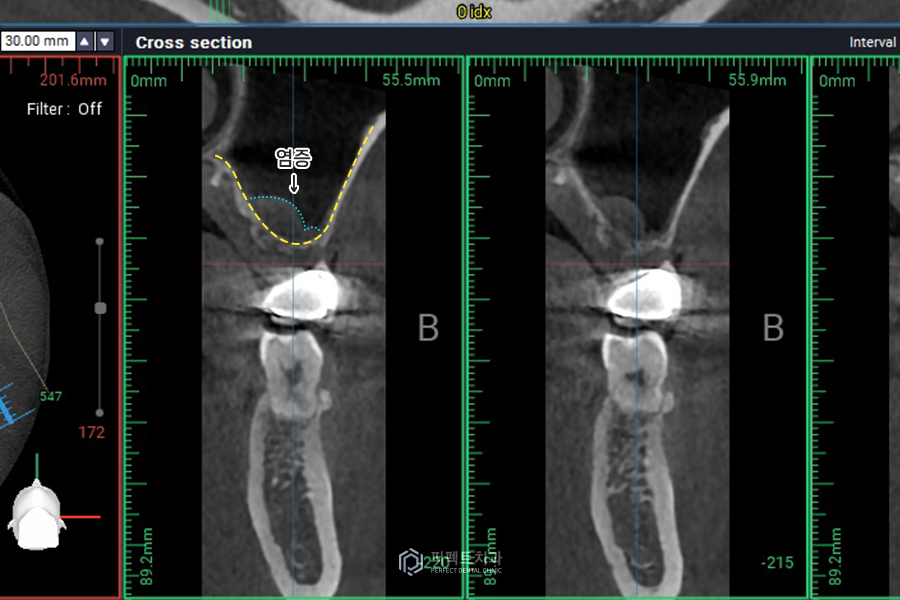

수술 하기 전 CT사진을 보시면 아까 말씀드렸듯이 뼈가 없는 부분은 거의 퇴화해서 둘러싸고 있는 치조골이 거의 없습니다. 사진상 보이는 하얀 부분이 뼈인데, 실제로 약 1mm정도의 뼈가 있고, 위에 표시된 부분은 염증, 검게 비어있는 부분이 상악동입니다.